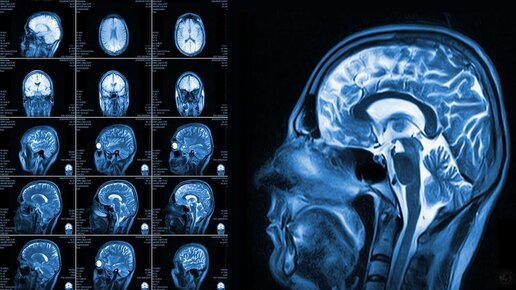

Магнитно-резонансная томография головного мозга – это современный метод обследования, который может дать важную информацию для диагностики опухолевых, воспалительных и демиелинизирующих заболеваний самого мозга и мозговых оболочек...

Человеческий мозг до сих пор считают самым сложным и малоизученным органом. МР-томография — приоритетное направление раннего выявления изменений в структурах центральной нервной системы. Безопасная и неинвазивная процедура помогает поставить верный диагноз. Разбираемся, как устроен МРТ головного мозга и когда следует пройти исследование. Что такое МРТ головного мозга Метод магнитно-резонансной томографии основан на взаимодействии электромагнитного поля высокой мощности и атомов водорода тканей органов...

МРТ головного мозга - это неинвазивный способ диагностики, который выполняется при наличии как хронических, так и острых симптомов заболеваний головного мозга. Процедура сканирования производится при помощи...

Здравствуйте, уважаемые читатели. Если вам или вашим близким назначили МРТ головного мозга, не стоит пугаться: это не приговор, а возможность понять, что происходит в вашем организме. Разобраться с этой темой — наша общая задача. А мы, врачи, готовы рассказать всё простым и понятным языком. Как говорил академик Лихачёв: «Здоровье — это не всё, но всё без здоровья — ничто». Особенно когда речь идёт о таком «центральном командном пункте» нашего тела, как головной мозг. МРТ — это метод диагностики, основанный на магнитном резонансе...